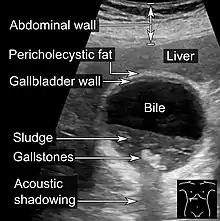

Gallstones

Gallstones form when the bile is saturated, usually with either cholesterol or bilirubin.[20] Most gallstones do not cause symptoms, with stones either remaining in the gallbladder or passed along the biliary system.[21] When symptoms occur, severe "colicky" pain in the upper right part of the abdomen is often felt.[20] If the stone blocks the gallbladder, inflammation known as cholecystitis may result. If the stone lodges in the biliary system, jaundice may occur; if the stone blocks the pancreatic duct, pancreatitis may occur.[21] Gallstones are diagnosed using ultrasound.[20] When a symptomatic gallstone occurs, it is often managed by waiting for it to be passed naturally.[21] Given the likelihood of recurrent gallstones, surgery to remove the gallbladder is often considered.[21] Some medication, such as ursodeoxycholic acid, may be used; lithotripsy, a non-invasive mechanical procedure used to break down the stones, may also be used.[21]

An ultrasound is often the first medical imaging test performed when gallbladder disease such as gallstones are suspected.[21] An abdominal X-ray or CT scan is another form of imaging that may be used to examine the gallbladder and surrounding organs.[21] Other imaging options include MRCP (magnetic resonance cholangiopancreatography), ERCP and percutaneous or intraoperative cholangiography.[21] A cholescintigraphy scan is a nuclear imaging procedure used to assess the condition of the gallbladder.[28]